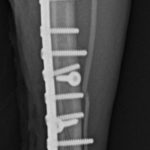

脛骨中央部らせん状骨折 階段で転んだワンチャンが、骨折をしてしまったので手術をしてほしいとの連絡があり対応しました。比較的、長い範囲でのらせん状骨折です。2本のポジションスクリューとプレーティングにより骨接合術を行いました。 症例カテゴリー 放射線治療整形外科軟部組織外科脳神経外科内科腫瘍外科救急・集中治療リハビリテーション科腫瘍内科内視鏡科脳神経科呼吸器外科中医・漢方猫の腎移植循環器科